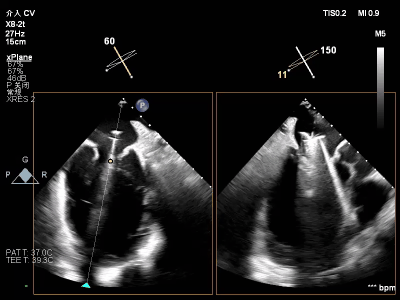

术前术后反流对比

【术后一周复查心超提示】二尖瓣钳夹术后,二尖瓣反流(轻度),夹合器固定,瓣口呈双孔结构,内外侧孔分别见微量反流,反流束VC分别 0.15cm、0.18cm,估测有效瓣口面积约2.5c㎡,舒张期瓣口前向最大血流速度 1.2m/s,平均压差3mmHg,左室射血分数(EF)值提升至35%,心功能显著改善。目前患者已顺利康复出院。